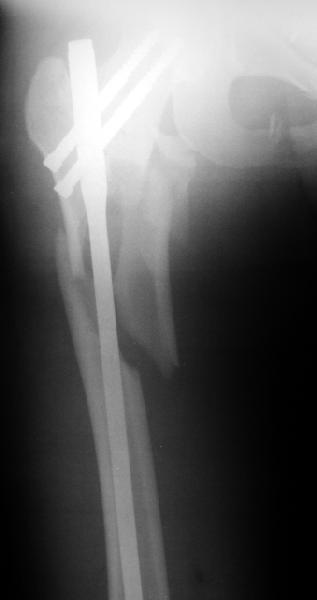

Оперировали вчера. Не сказать, что все прошло гладко - вертельная область была расколота и в сагиттальной, и во фронтальной плоскости, гвоздь попал в перелом и сместился кзади, что заметили уже после введения винтов, пришлось все извлечь и переставить. Снимки в приложении. Буду признателен за комментарии.

Если честно, мне не нравится стояние отломков

проксимального отдела. На мой взгляд причина в недостаточной осевой тракции сегмента перед этапом дистального блокирования. Если это действительно так, я бы попробовалудалить дистальные блокирующие винты, дать осевую тракцию(дистрактор, ортопедический стол, др.) и повторное дистальное

блокирование.

уважаемый А.Ч.! Не уверен, что отломки сопоставлены хорошо. Особенно плохо лбстоят дела с малым вертелом. Клинический исход по-видимому будет неудовлетворительным.